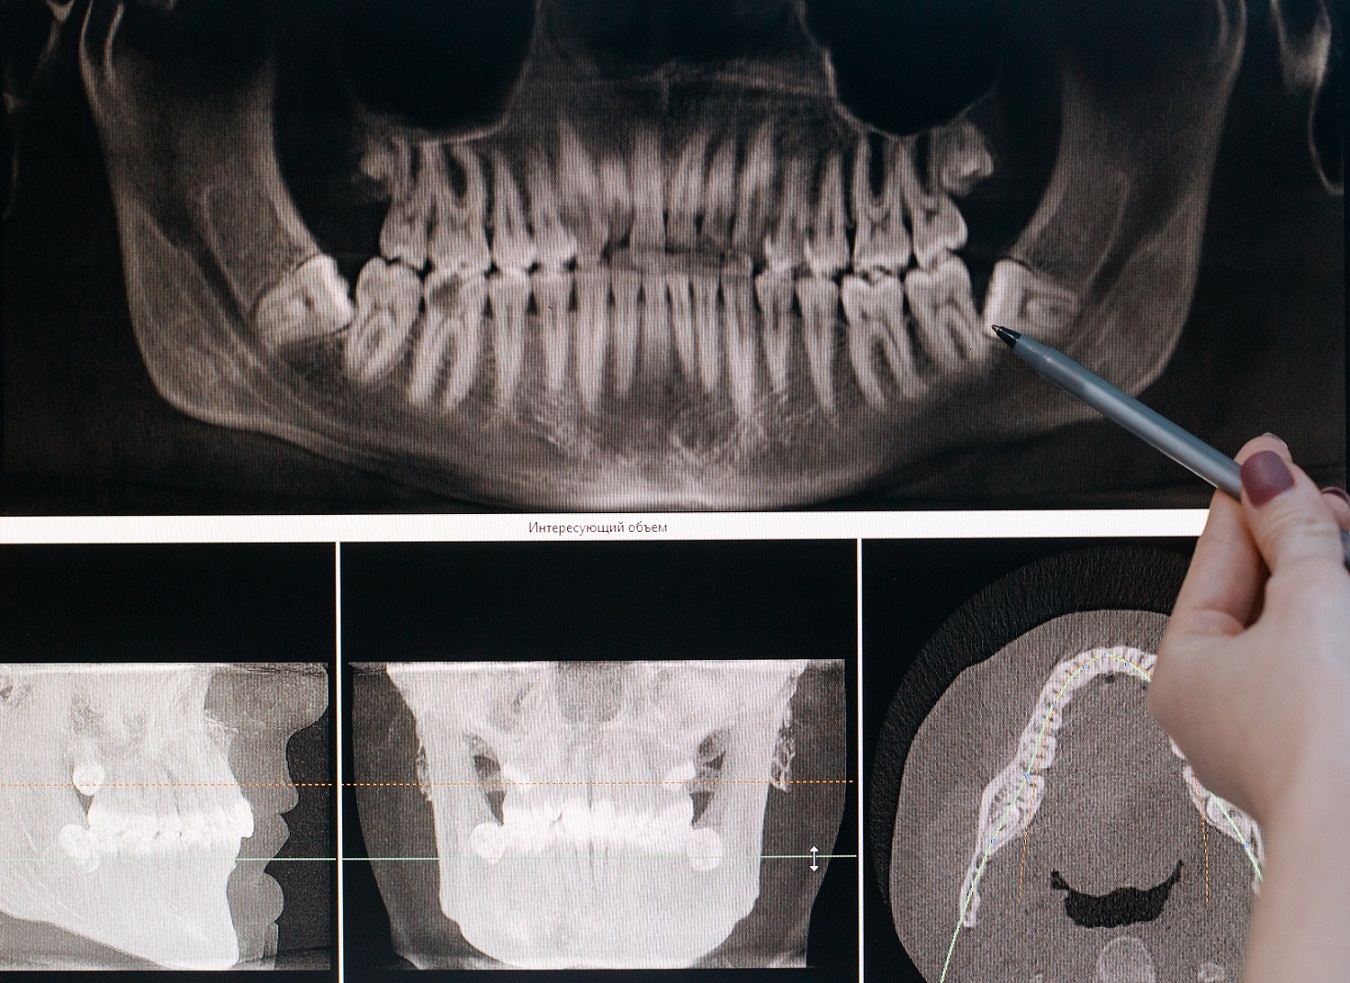

Il arrive également que les dents de sagesse poussent en biais ou demeurent tout simplement dans la gencive. Elles peuvent alors appuyer sur les autres dents, entraînant ainsi des complications, ou blessant la gencive.

De plus, toute anomalie dans leur croissance peut provoquer des caries importantes. En effet, en plus d'être difficiles à atteindre avec la brosse à dents, elles peuvent causer des dégâts sur les molaires qui les entourent, soit en transmettant une infection, soit en provoquant une carie.